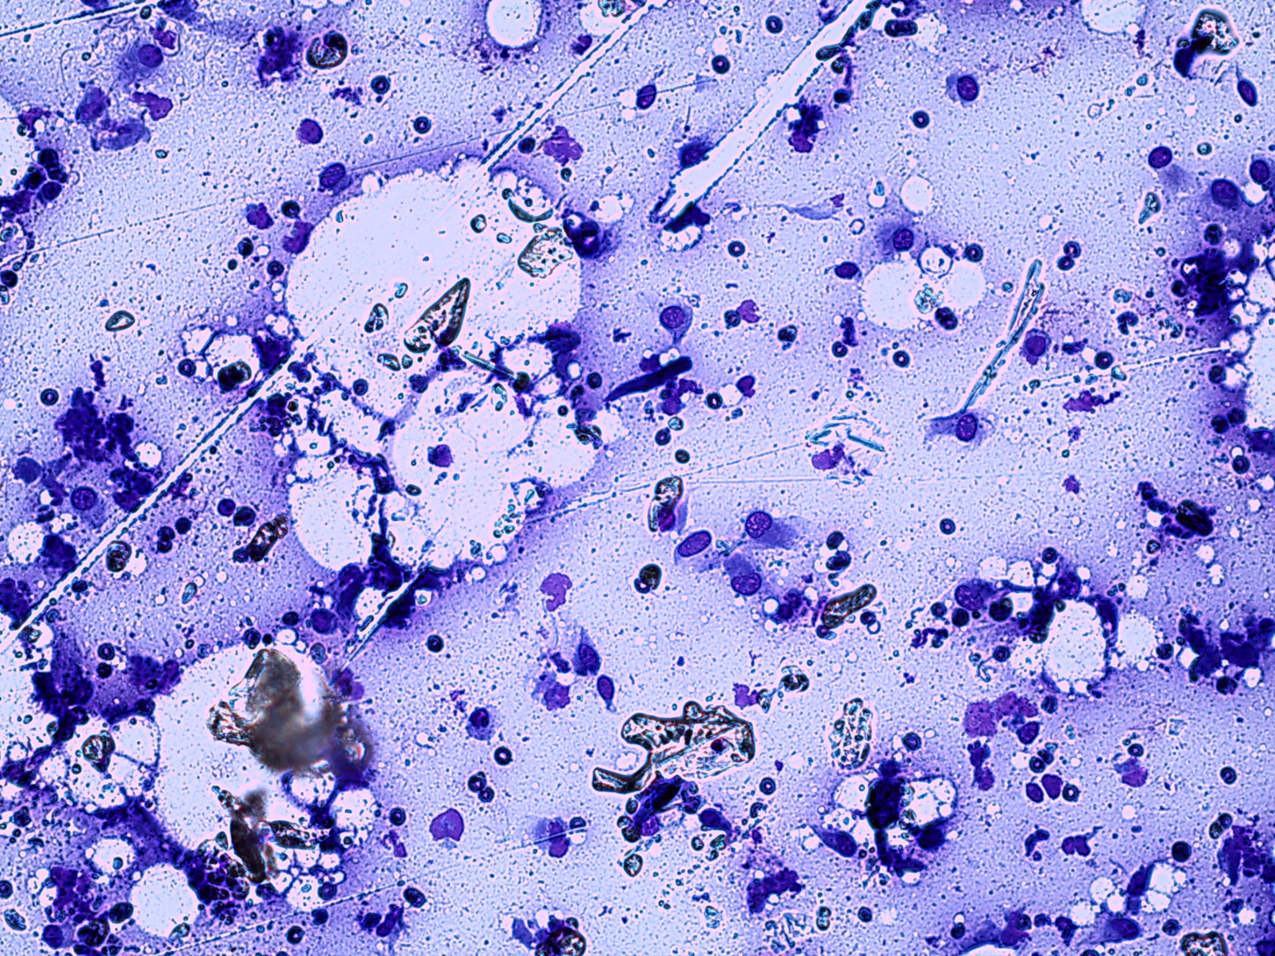

how do we do a cytological examination

Low power review (x10 objective)

Good places to look at

Quality

Any/many cells?

Well/poorly preserved?

Background

Haemorrhage, granules, protein, matrix, debris, disrupted cells

Predominant cells

Neutrophils? Other cells?

Cells (x 40 or oil)

Individual or organised

Single or mixed population?

Cell size, shape, variation?

Nuclear size, shape, variation, abnormal mitoses?